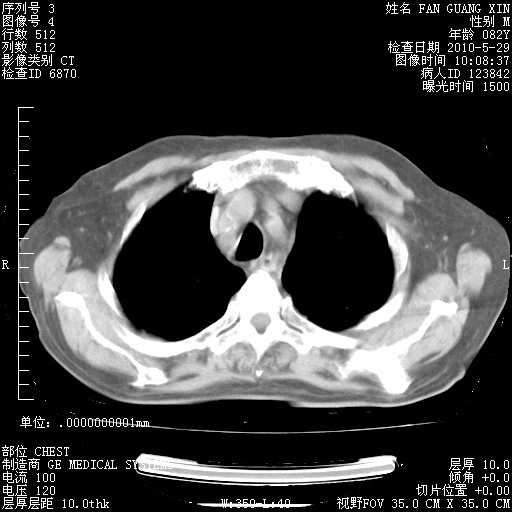

发表于 2010-5-19 19:23

还需要哪些辅助检查?我们医院排除真菌感染没有任何检验方法,胸片好像能够排除肺部真菌感染。

补充:ENA化验全部阴性。免疫五项(IgG、IgA、IgM、C3、C4)只有C4略高。